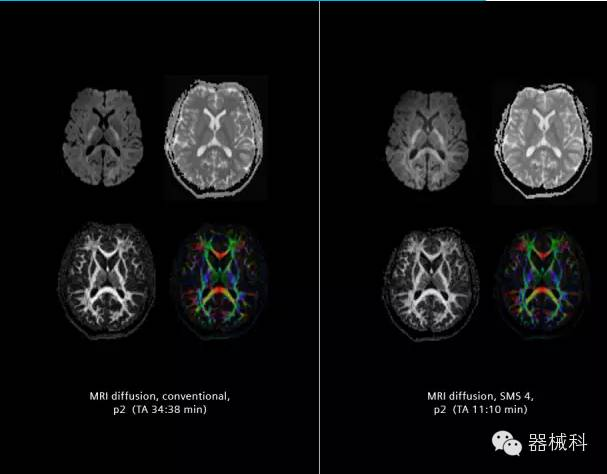

在2015年RSNA上,西門子隆重發(fā)布了Simultaneous Multi-slices 技術(shù)(即同時(shí)多層采集技術(shù),簡(jiǎn)稱SMS),這是磁共振掃描技術(shù)中第一次引入“同時(shí)多層”的概念,此概念技術(shù)的發(fā)布,將對(duì)未來(lái)磁共振成像領(lǐng)域帶來(lái)巨大的變革!

· 2012年,麻省總醫(yī)院Kawin Setsompop等在西門子7T 磁共振上獲得了使用SMS技術(shù)的得到的同時(shí)多層diffusion和fMRI圖像,并得出結(jié)論,采用全新的SMS技術(shù),可以大幅度提高空間分辨率和采集速度。

SMS技術(shù)可以將原本用于科研的高級(jí)成像技術(shù)轉(zhuǎn)化成臨床常規(guī)。

SMS可以有效提升高級(jí)功能成像精準(zhǔn)度。

擁有了SMS“同時(shí)多層”采集技術(shù)之后,用戶可以在非常短的時(shí)間內(nèi)完成MR掃描,結(jié)合西門子靜音技術(shù),大大提高患者的舒適性,或在單位時(shí)間內(nèi)采集更多的數(shù)據(jù),也可以得到高精度、高準(zhǔn)確性、大數(shù)量的功能成像數(shù)據(jù),為臨床和科研提供強(qiáng)大的支持。專家認(rèn)為,SMS“同時(shí)多層”采集技術(shù)未來(lái)在 提高成像質(zhì)量、外科手術(shù)計(jì)劃、降低術(shù)后神經(jīng)功能缺陷、提高fMRI的時(shí)間采集效率、提高靜息態(tài)功能磁共振數(shù)據(jù)質(zhì)量等方面將帶來(lái)深遠(yuǎn)影響,希望該技術(shù)可以盡早面世,引領(lǐng)磁共振進(jìn)入多層時(shí)代!